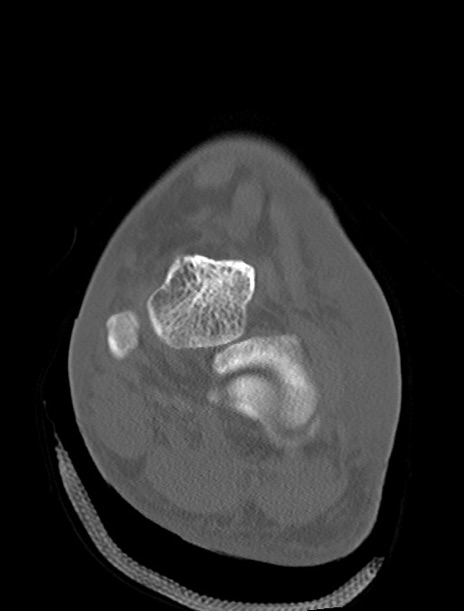

症例37 左足関節CT(冠状断像)

左足関節CT

横断像